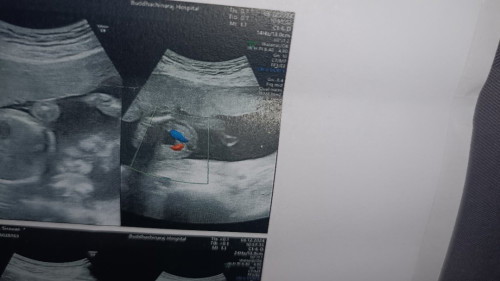

ไปหาหามาเมื่อวานก่อนค่ะเป็นการซาวด์ดูโครงสร้างของน้อง แต่คุณหมอไม่บอกเพศว่าน้องมีช้างหรือกีบ...แม่ๆพอมองออกมั้ยคะว่าน้องมีช้างหรือมีกีบ🙏🙏

กี่วีคคะ ยังไม่ถึงเวลาที่จะดูเพศหรือป้าว แต่ละเดือนจะตรวจไม่เหมือนกันค่ะ